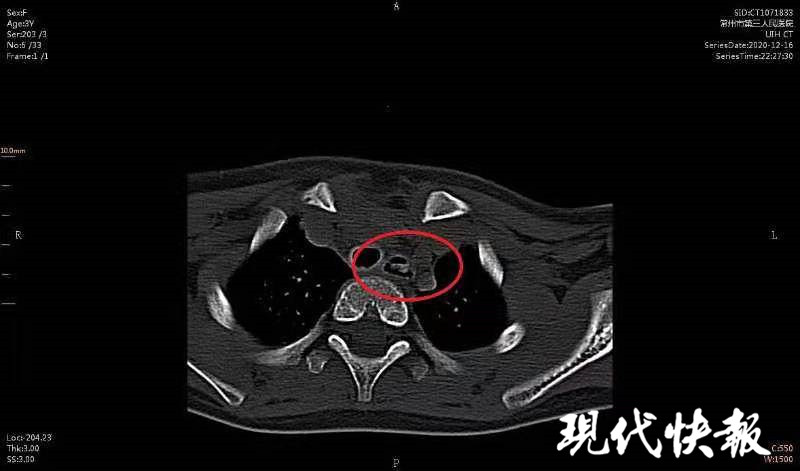

△CT顯示女童食道內(nèi)有異物

醫(yī)生檢查發(fā)現(xiàn),異物就卡在歡歡的食道里。“食道并不是一根直直的管道,它是有狹窄部位的,其中最容易引起異物嵌頓的狹窄有3處,處處都很危險(xiǎn)的。第1處狹窄位于食管的起端,是咽與食管的交接處;第2處狹窄在食管入口以下7厘米處,位于左主支氣管后方與之交叉處;第3處狹窄是食管通過(guò)膈肌的裂孔處。”常州三院耳鼻咽喉科副主任醫(yī)師陸曉宇說(shuō)。